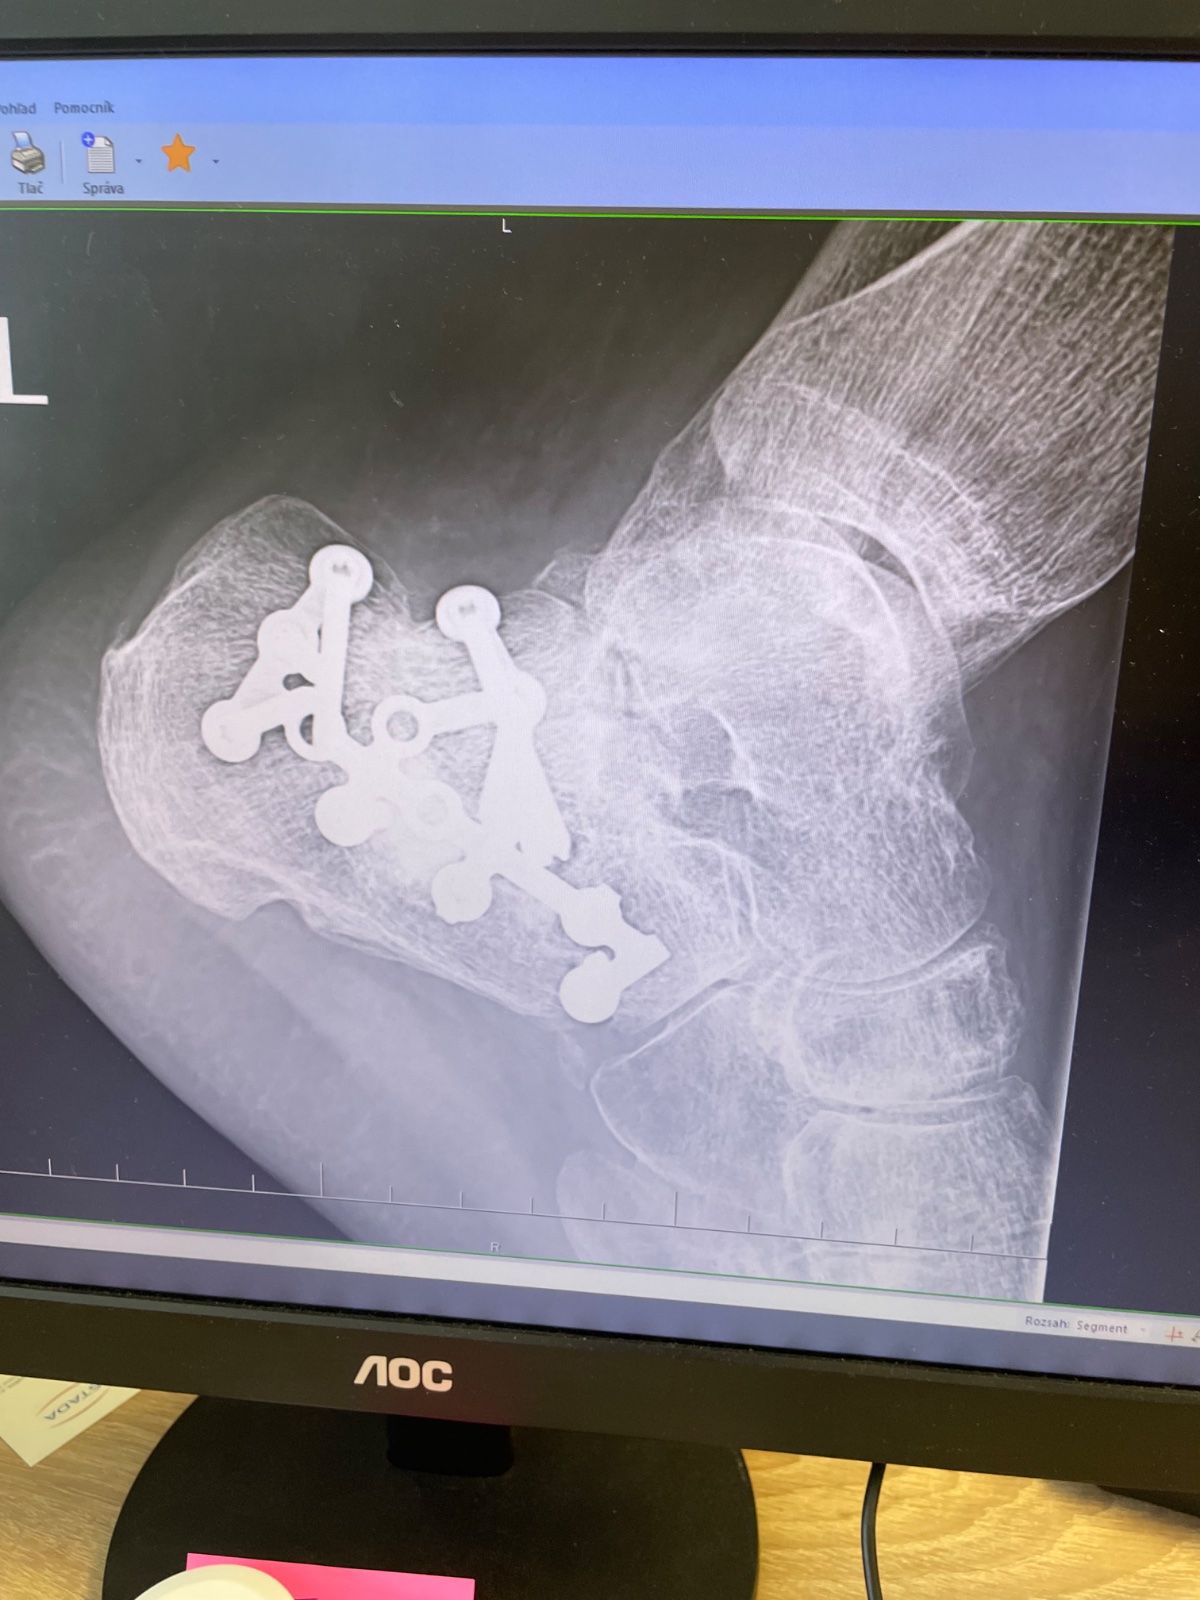

Zdravím, no môj snímok vyzerá podobne, tiež zošrobované a samý kov, ako noha Robocopa. Som osemnásť mesiacov a svetlo stále nevidím. Prejdem, tak kilometer a potom koniec. Teraz som bol na konzultáciách v NR a potvrdené KE, že má čaká ďalšia operácia. Členok, že vraj s najväčšou pravdepodobnosťou bol poškodený roztrieštnou pätou. Teraz je tam kov, ktorý bude nutné odstrániť a s tým spojené možné komplikácie a vyplnenie štepom.